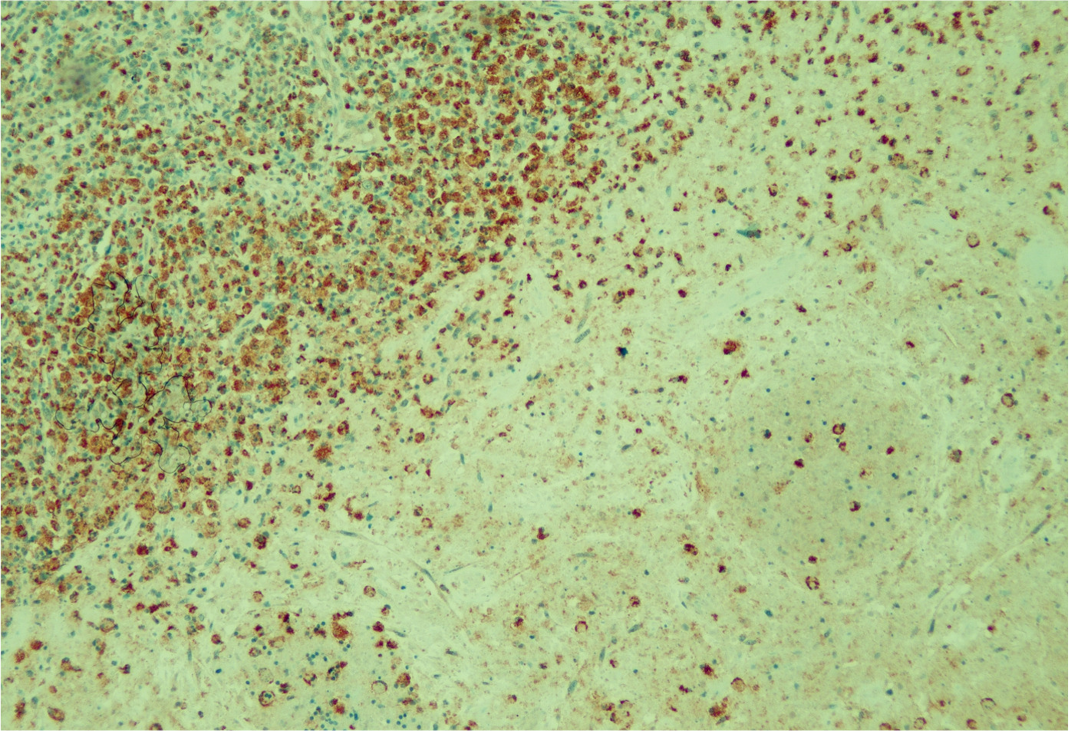

Antibiyoterapinin üçüncü gününde ateş yanıtı alınamayan, genel durumu ve oral alımı bozulan hastada antibiyoterapi moksifloksasin 1×400 mg İV şeklinde genişletildi ve histopatolojik tanı için eksizyonel biyopsi yapıldı. Takiplerinde moksifloksasine rağmen ateş yüksekliği devam eden hastanın tularemi serolojisi ve IGRA testi negatif olarak sonuçlandı. Histopatolojik incelemede, kapsülü yer yer kalınlaşmış ve olağan yapısı bozulmuş lenf nodu dokusunda, histiyositlerden, eozinofilik granüler materyalden ve apoptotik cisimciklerden oluşan, merkezinde nekroz izlenen soluk alanlar görüldü. İmmünohistokimyasal çalışmalarda nekroz alanlarında ve çevresindeki hücrelerde myeloperoksidaz, CD123 (plazmositoid dendritik hücrelerde), CD68 ve CD14 (histiyositlerde), CD15 (polimorfonükleer lökositlerde), CD30 (aktive hücrelerde), CD3, CD4, CD8 ve CD20 (lenfosit alt gruplarında) pozitif reaksiyon gösterdi (Resim 2).